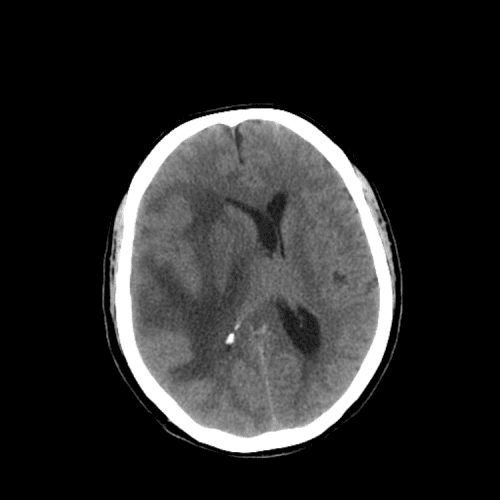

Lacunar infarct

Basilar artery thrombosis

Watershed ischemia

Cardioembolic infarcts

Deep venous infarct